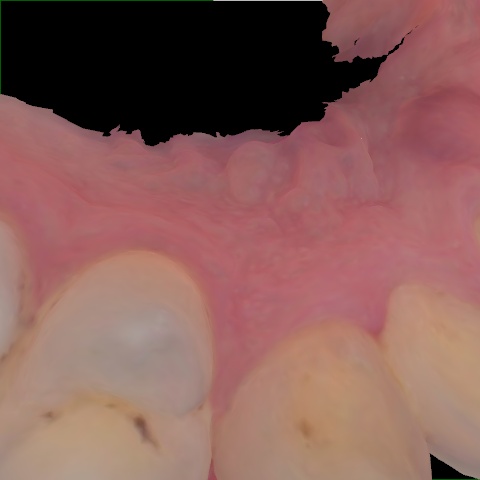

Image 507 / 2000

NHD39969

Annotated as "Good"

Original Image Rendering Image